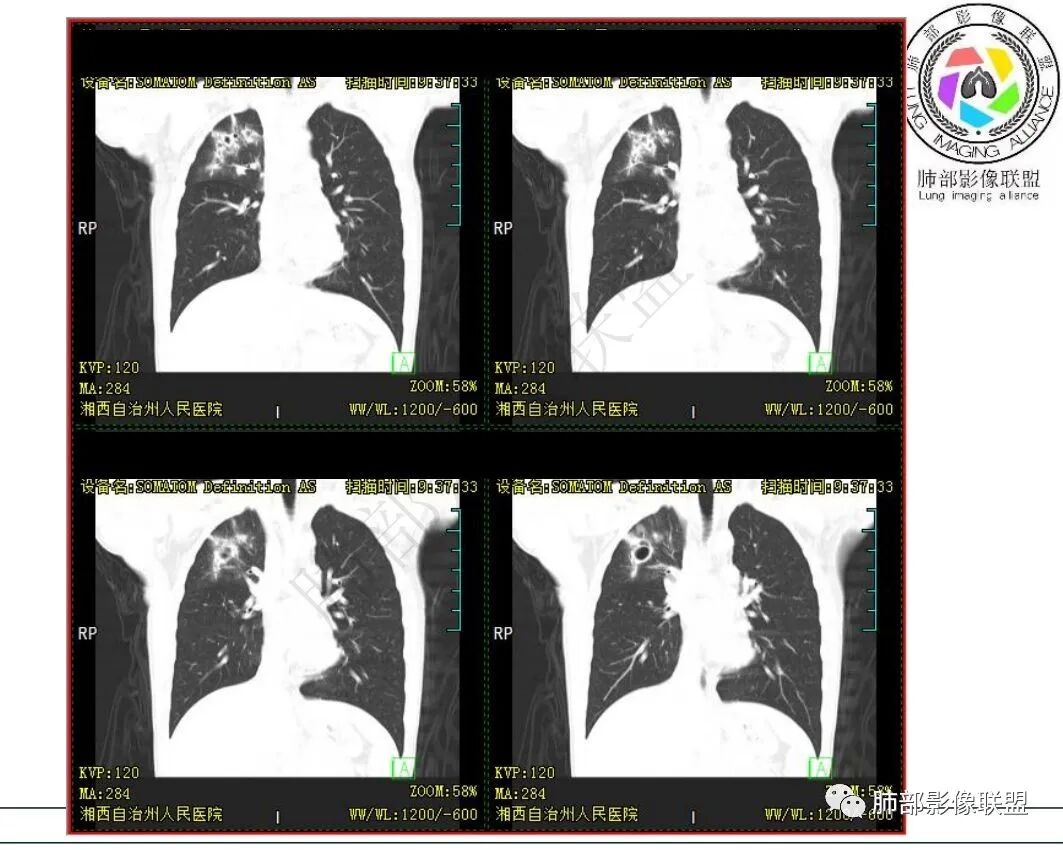

影像:右肺上叶多发实变影结节影,边界模糊,边缘收缩,伴多发空洞,洞壁光滑,部分支气管壁增厚。

3.首次CT提示:右肺上叶多发结节影及实变影,簇状分布,周围散在磨玻璃影,结节内多类圆形空洞,内壁光整,有一定张力,偶见液平。部分支气管壁增厚。

考虑良性感染性病变可能。